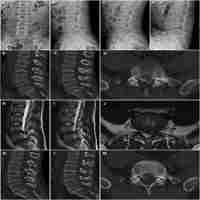

| Description | Objective: To make lumbar discectomy simple and feasible, we developed an endoscopic surgical technique that uses a Thoracoport as a tubular retractor. Surgical technique: The patient was placed in a 60-degree forwardly inclined lateral position with the side of the lesion on the top. After radiological confirmation of the index level, a Thoracoport was inserted through a 2-cm paramedian transverse skin incision. A 0-degree rod lens endoscope was mounted to a scope holder and placed into the retractor for magnification and illumination. Laminotomy was performed with a high-speed drill to reach the insertion of the yellow ligament to the upper lamina. A 2-mm undercutting of the upper facet was performed with a punch to expose the lateral edge of the nerve root. Surgical instruments were inserted next to the endoscope for manipulation. The herniated disc was identified and removed with pituitary rongeurs as in a standard microdiscectomy. With this technique, a sufficient amount of bone is resected to expose the disc lateral to the nerve root; hemostasis is easily achieved and the incidence of nerve root injury is reduced. Conclusion: We have successfully performed an endoscopic lumbar discectomy in 20 patients by using a Thoracoport as a tubular retractor. No specially designed instruments were required. This technique was a safe and effective minimally invasive approach to treating lumbar disc disease according to our preliminary experience. |